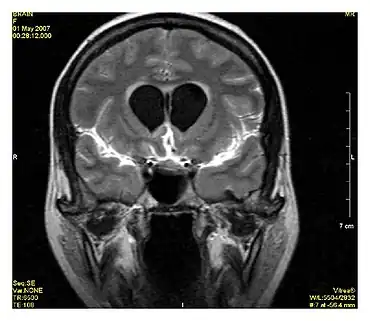

Angiography

Magnetic resonance angiography

Magnetic resonance angiography (MRA) generates pictures of the arteries to evaluate them for stenosis (abnormal narrowing) or aneurysms (vessel wall dilatations, at risk of rupture). MRA is often used to evaluate the arteries of the neck and brain, the thoracic and abdominal aorta, the renal arteries, and the legs (called a "run-off"). A variety of techniques can be used to generate the pictures, such as administration of a paramagnetic contrast agent (gadolinium) or using a technique known as "flow-related enhancement" (e.g., 2D and 3D time-of-flight sequences), where most of the signal on an image is due to blood that recently moved into that plane (see also FLASH MRI).[39]

Techniques involving phase accumulation (known as phase contrast angiography) can also be used to generate flow velocity maps easily and accurately. Magnetic resonance venography (MRV) is a similar procedure that is used to image veins. In this method, the tissue is now excited inferiorly, while the signal is gathered in the plane immediately superior to the excitation plane—thus imaging the venous blood that recently moved from the excited plane.[40]